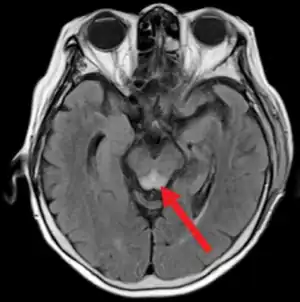

Magnetic resonance imaging shows characteristic Wernicke's encephalopathy with T2 signal hyper-intensity in the periaqueductal area (arrow).

Diagnosis of Wernicke encephalopathy or disease is made clinically.[42][55] Caine et al. in 1997 established criteria that Wernicke encephalopathy can be diagnosed in any patient with just two or more of the main symptoms noted above.[56] The sensitivity of the diagnosis by the classic triad was 23% but increased to 85% taking two or more of the four classic features. This criteria is challenged because all the cases he studied were people who drank excessive amounts of alcohol. Some consider it sufficient to suspect the presence of the disease with only one of the principal symptoms.[57] Some British hospital protocols suspect WE with any one of these symptoms: confusion, decreased consciousness level (or unconsciousness, stupor or coma), memory loss, ataxia or unsteadiness, ophthalmoplegia or nystagmus, and unexplained hypotension with hypothermia. The presence of only one sign should be sufficient for treatment.[58]

As a much more diverse range of symptoms has been found frequently in patients it is necessary to search for new diagnostic criteria, however Wernicke encephalopathy remains a clinically-diagnosed condition. Neither the MR, nor serum measurements related to thiamine are sufficient diagnostic markers in all cases. However, as described by Zuccoli et al. in several papers the involvement of the cranial nerve nuclei and central gray matter on MRI, is very specific to WE in the appropriate clinical setting.[53] Non-recovery upon supplementation with thiamine is inconclusive.

The sensitivity of MR was 53% and the specificity was 93%. The reversible cytotoxic edema was considered the most characteristic lesion of WE. The location of the lesions were more frequently atypical among people who drank appropriate amounts of alcohol, while typical contrast enhancement in the thalamus and the mammillary bodies was observed frequently associated with alcohol misuse.[53] These abnormalities may include:[7]